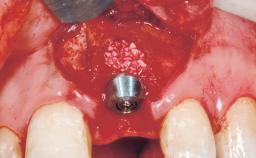

Late Placement of an Implant in a Maxillary Left Central Incisor Site

Bone Augmentation Horizontal|Staged

Augmentation Materials Xenogenous|Membrane

Bone Volume Deficient horizontally, requiring prior grafting